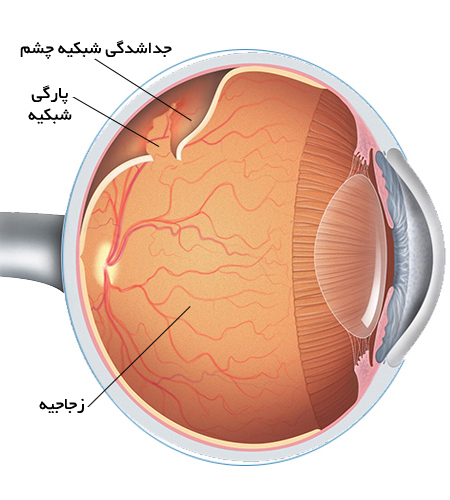

پارگی شبکیه یکی از اختلالات جدی چشم است که در آن، شبکیه که لایه نازک و حساسی در پشت چشم است، از جایگاه اصلی خود جدا میشود. این مشکل میتواند منجر به از دست دادن دید مرکزی یا حتی نابینایی کامل شود، بهویژه اگر درمان به موقع انجام نشود. پارگی شبکیه بیشتر در افرادی رخ میدهد که به دلایل مختلف، بافت شبکیهشان آسیبپذیرتر است. در موارد شدید، این وضعیت میتواند به جداشدگی کامل شبکیه منجر شود که نیاز به جراحی فوری دارد.

در موارد شدید که پارگی شبکیه به جداشدگی منجر شده است، جراحی ویترکتومی انجام میشود که شامل حذف بخشی از زجاجیه و بازگرداندن شبکیه به جای اصلی خود است.

در این روش، نوار سیلیکونی به دور چشم بسته میشود که فشار لازم را برای تثبیت شبکیه فراهم میکند.